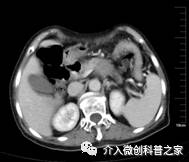

专家介绍说,以前,临床治疗胰腺癌多采用手术以及放化疗,但是随着我国医疗技术的不断完善,胰腺癌介入治疗也被很多患者采用,中晚期胰腺癌的介入治疗方案主要有胰腺癌供血动脉化疗药物灌注治疗,胰腺癌内部放射性粒子近距离照射治疗,如果胰腺癌浸及胆总管引起胆道梗阻性黄疸可以行胆道支架植入治疗,胰腺癌浸及十二指肠引起肠道梗阻可以行十二指肠支架植入治疗,下面用图片和文字简单介绍给大家一下我们科的介入手术病例。

中晚期腺癌内部放射性粒子近距离照射治疗

(近距离照射杀死癌细胞、止痛效果好)